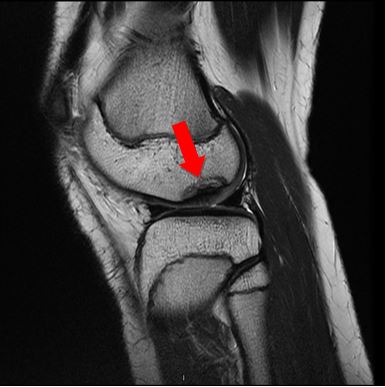

Diagnoosi ja hoitomuodon valinta perustuvat lääkärin tekemään polven tutkimukseen sekä tapauskohtaisesti harkittaviin kuvantamistutkimuksiin (röntgentutkimus ja / tai magneettitutkimus).